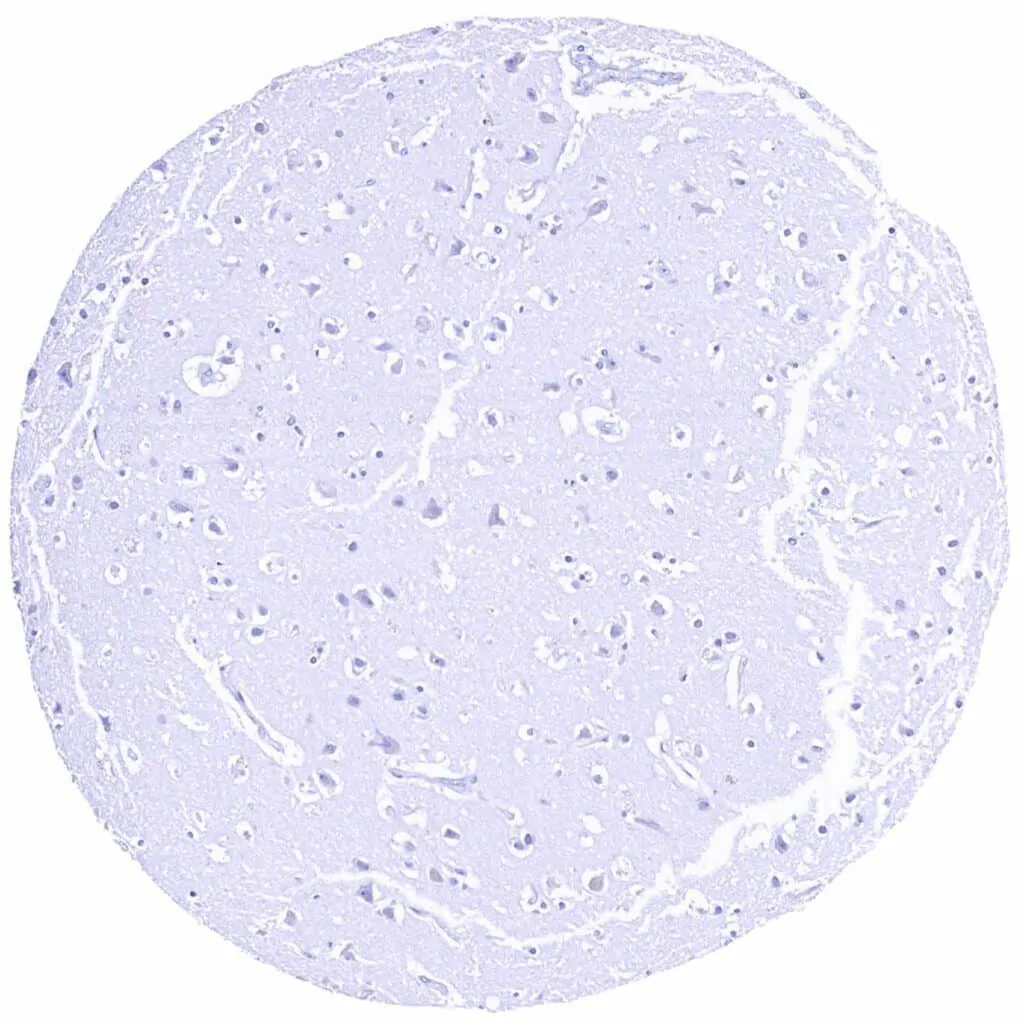

Cerebrum, grey matter